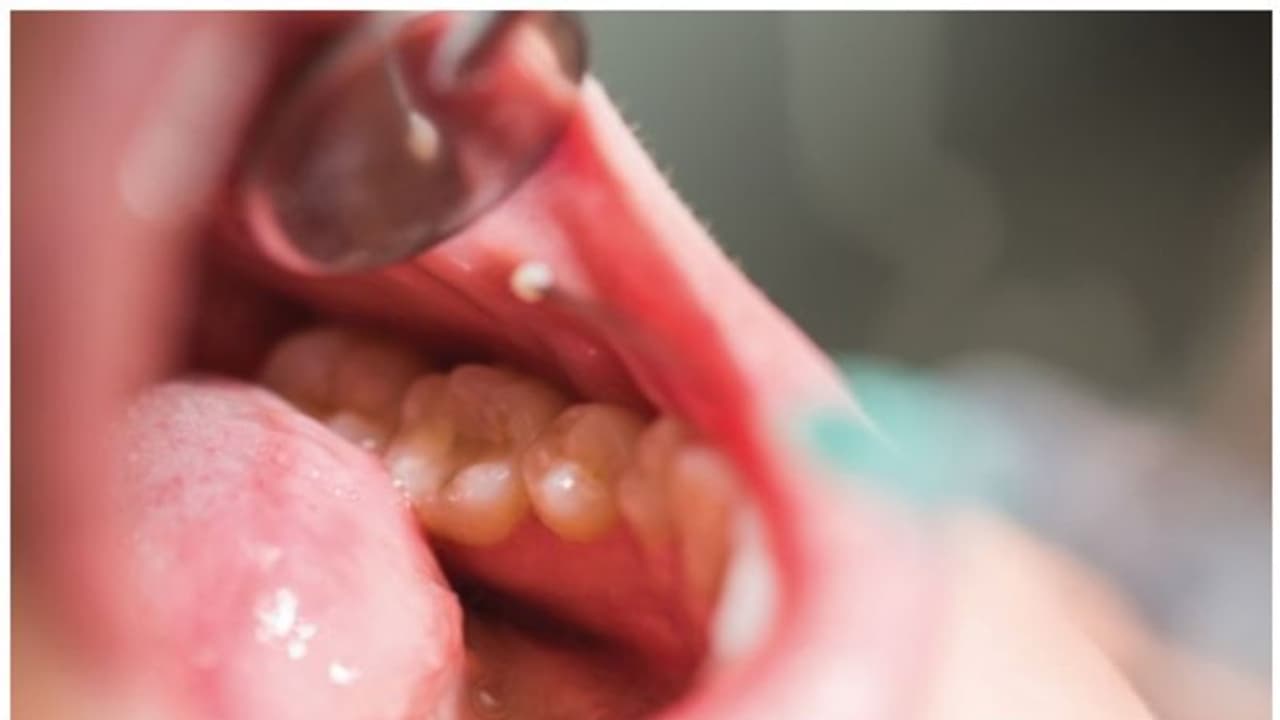

വായിലെ ക്യാൻസർ ; ലക്ഷണങ്ങൾ എന്തൊക്കെ? (Symptoms of mouth cancer)

1. വായിൽ പതിവായി പുണ്ണ് വരികയും അത് ഉണങ്ങാതിരിക്കുകയും ചെയ്യുക.

2. വെള്ളയോ, ചുവന്നതോ, രണ്ടും കൂടിയതോ ആയ മാറ്റങ്ങൾ നാവിലോ മോണയിലോ കവിളിലോ കാണുക.

3. ഭക്ഷണം ചാവക്കാനോ ഇറക്കാനോ ഉള്ള പ്രയാസം.

4. വായയുടെ ഏതെങ്കിലും ഭാഗത്ത് തടിപ്പോ മുഴയോ കല്ലിപ്പോ കാണുക.

5. വായിലോ, താടിയെല്ലിന്റെ ഭാഗത്തോ വേദന അനുഭവപ്പെടുക.

6. വായിൽ നിന്നും അകാരണമായ രക്തസ്രാവം ഉണ്ടാവുക.